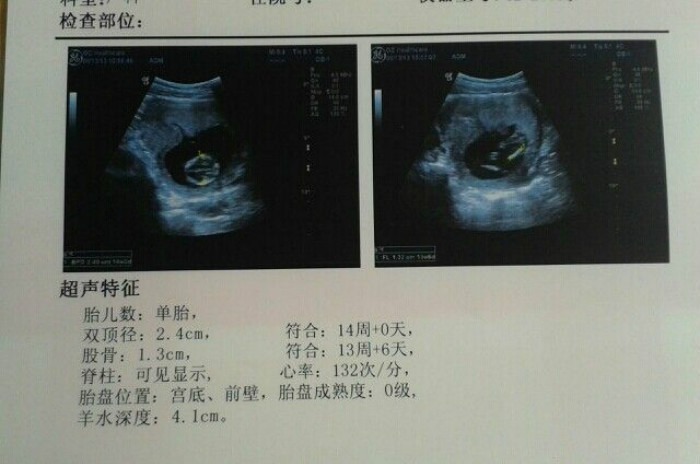

12周这个时候妈妈就要建卡了,除了询问一些基本情况之外,还要做一个全面的体检。除了正常的体检之外,还要做一个非常重要的nt筛查,其实这主要是为了检查宝宝有没有染色体变异所引起的疾病。如果这个检查通过了,那说明他的染色体是很正常的,可以继续发育。